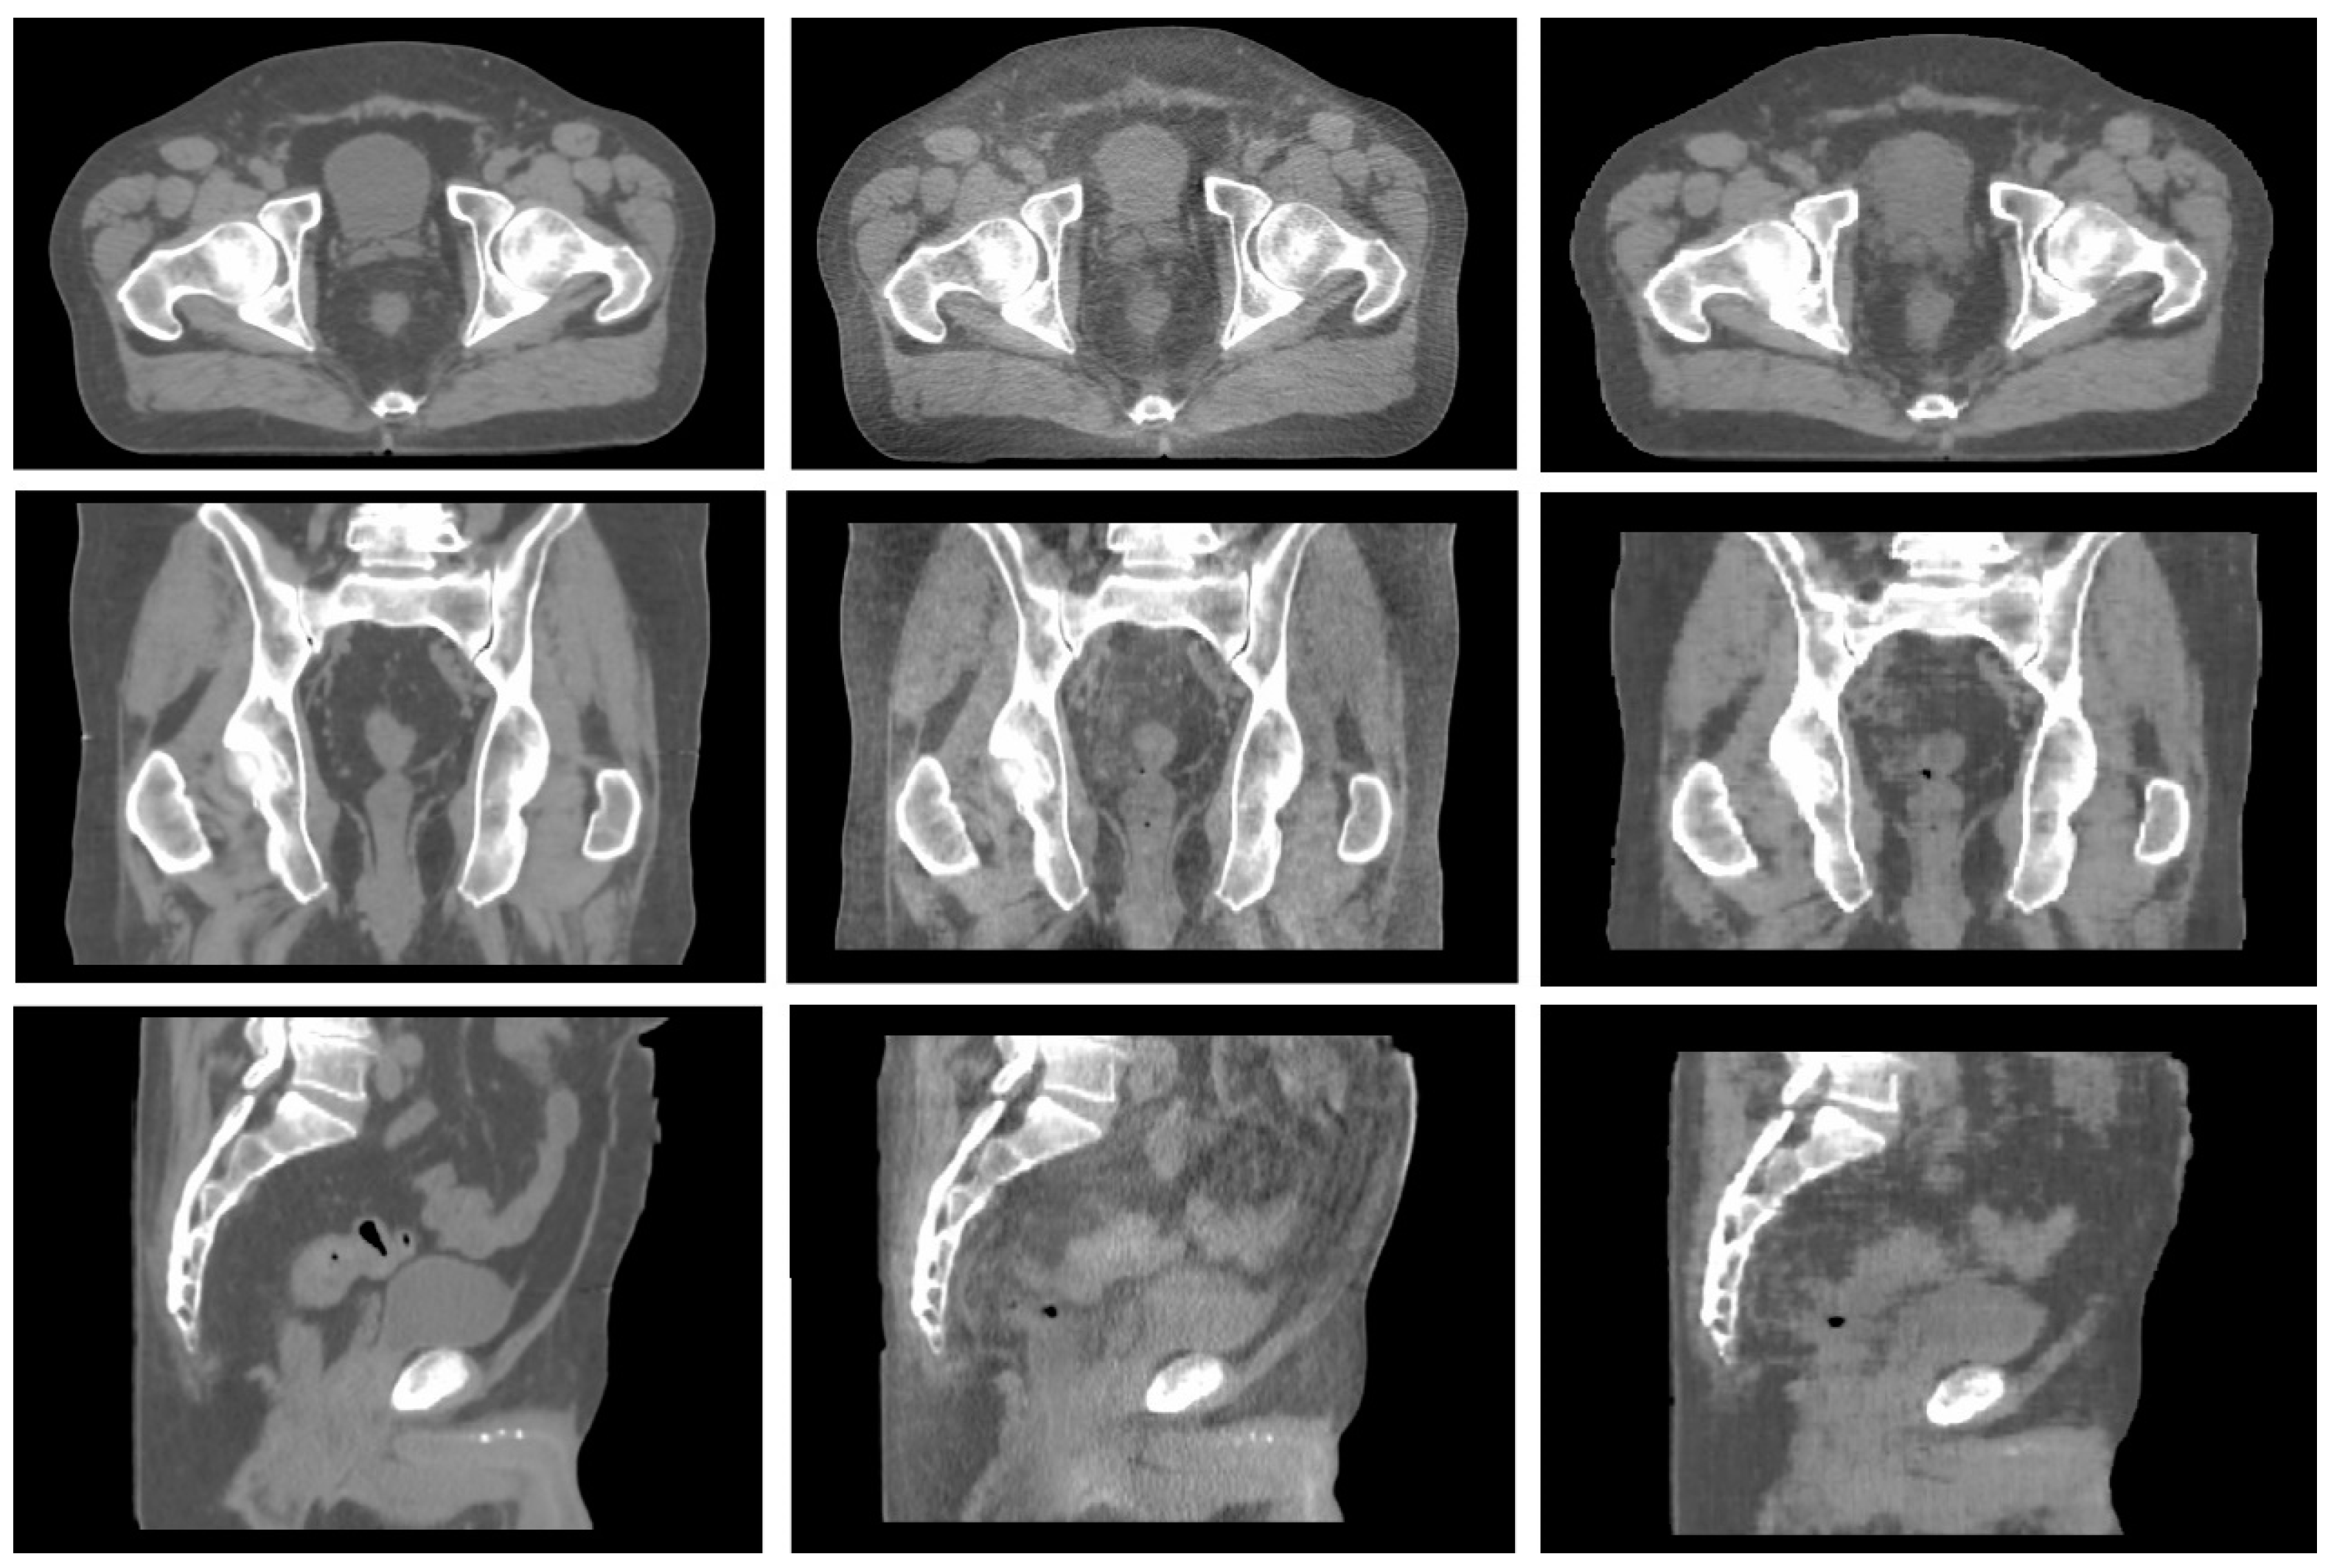

- High anatomical correspondence in terms of bony anatomy.

- Shape correspondence related to the patient’s body is displayed in the two images.

- High agreement in terms of location and volume of air pockets.

- No presence of image artifacts in CBCT due to the presence of large air bubbles.

- No presence of cut images due to a reduced field of view (FOV), a condition typical of apical CBCT slices.